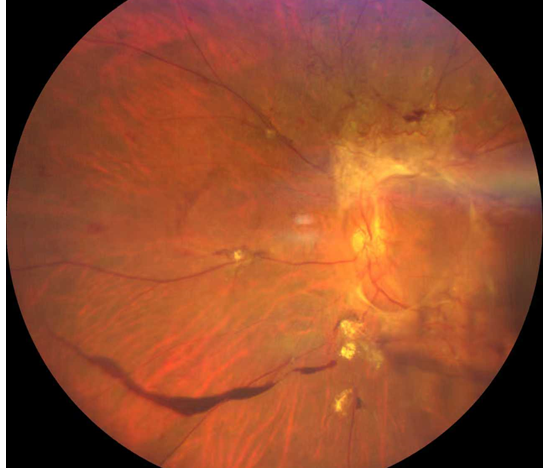

雙眼被確診為Ⅱ期增殖性糖尿病視網(wǎng)膜病變(以下簡(jiǎn)稱“糖網(wǎng)”),并伴有黃斑水腫。

糖尿病視網(wǎng)膜病變